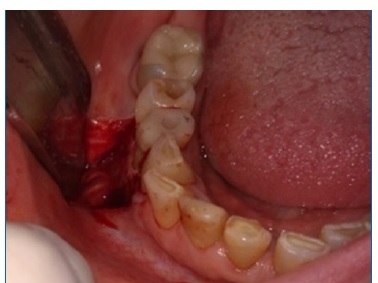

Além disso, não foi diagnosticada lesão mandibular no primeiro episódio. A paciente comunicou que omitiu o diagnóstico durante a anamnese por não acreditar ter relação com a odontalgia, e por ter feito exames laboratoriais e de imagem de corpo inteiro que descartaram qualquer sinal do mieloma, há cerca de trinta dias. Realizou-se punção aspirativa por agulha fina da área entumecida, não sendo observado presença de material líquido, sendo então optado pela realização de biopsia incisional (Figura 4), sob anestesia local, devido a necessidade de conclusão do diagnóstico. Durante o procedimento cirúrgico foi possível evidenciar um nódulo de superfície lisa, brilhante, avermelhada com estrias esbranquiçadas e friável a manipulação. A análise histopatológica (Figuras 5, 6 e 7), corada com Hematoxilina e Eosina, revelou proliferação de células de morfologia plasmocitóide, que apresentavam atipia, cromatina nuclear pontilhada e invasão do tecido conjuntivo, conferindo o laudo de mieloma múltiplo, sem necessidade de marcação imunohistoquímica, devido ao diagnóstico dessa lesão no passado.